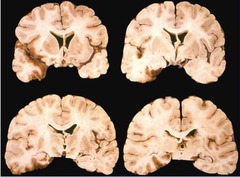

vascular dementia gross findings

Front

cerebral atrophy and ex vacuo hydrocephalus from reduction in white matter multifocal lacunar infarcts